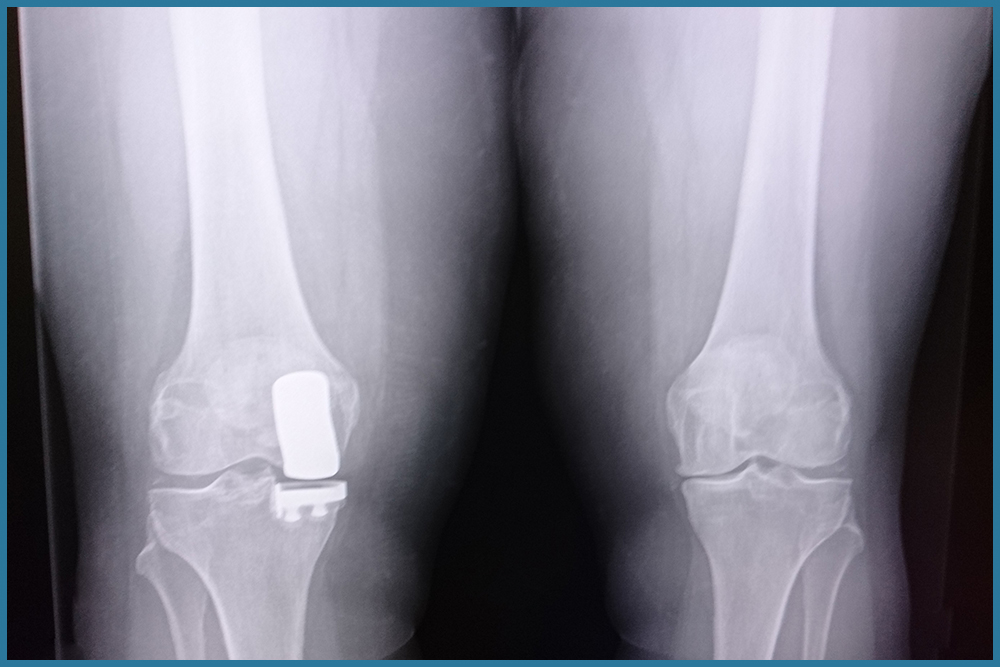

La protesi del ginocchio

Come il nostro Centro Artrosi può aiutarti Uno degli approcci curativi dell’artrosi di ginocchio, qualora la degenerazione dell’articolazione sia troppo avanzata per un approccio conservativo, è sicuramente l’innesto protesico che può essere di diversi tipi. Le protesi del ginocchio si distinguono...